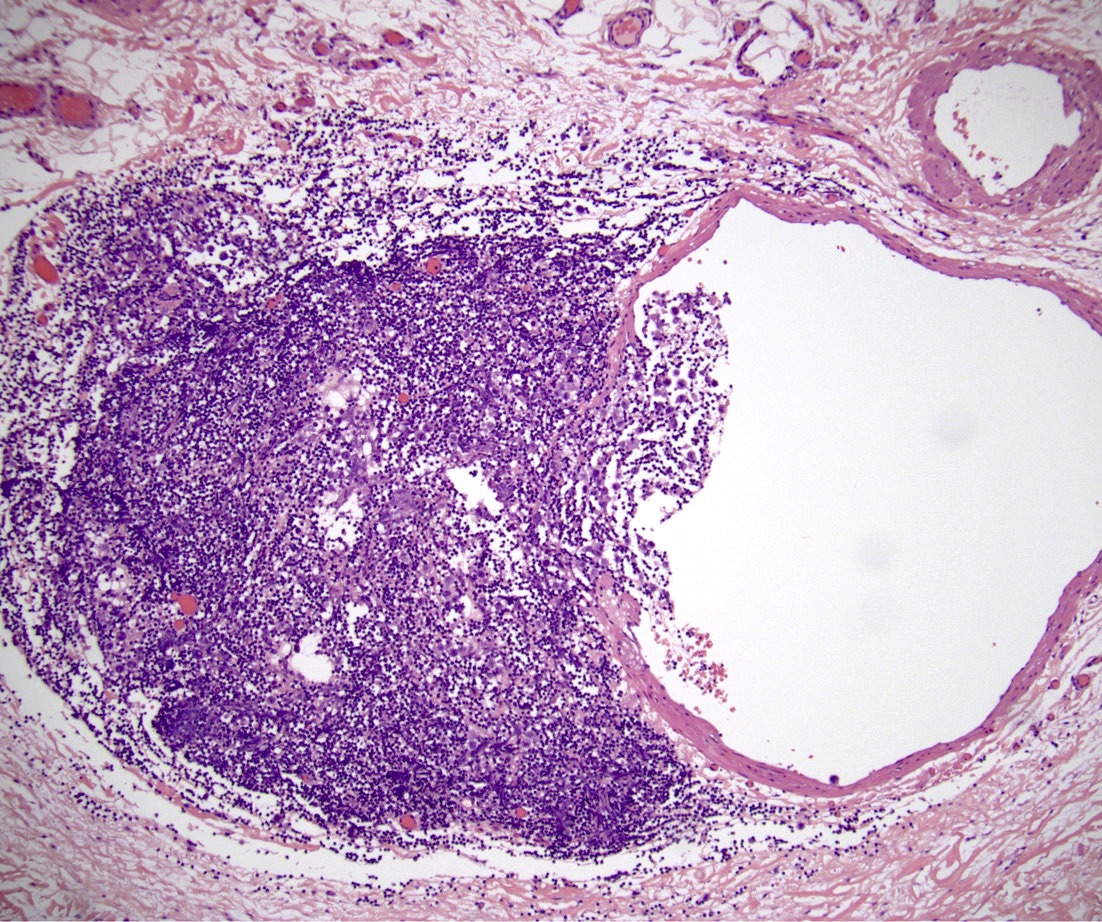

Microscopic (histologic) images

Board review style question #1

In a postpubertal testicular germ cell tumor, lymphovascular (shown above), hilar fat, epididymal and tunica vaginalis invasion are all a part of which pT category?

Board review style answer #1

D. pT2. Lymphovascular, hilar fat, epididymal and tunica vaginalis invasion are all a part of the pT2 category for testicular germ cell tumors. Lymphovascular invasion by embryonal carcinoma is shown in the image.

Comment Here Reference: